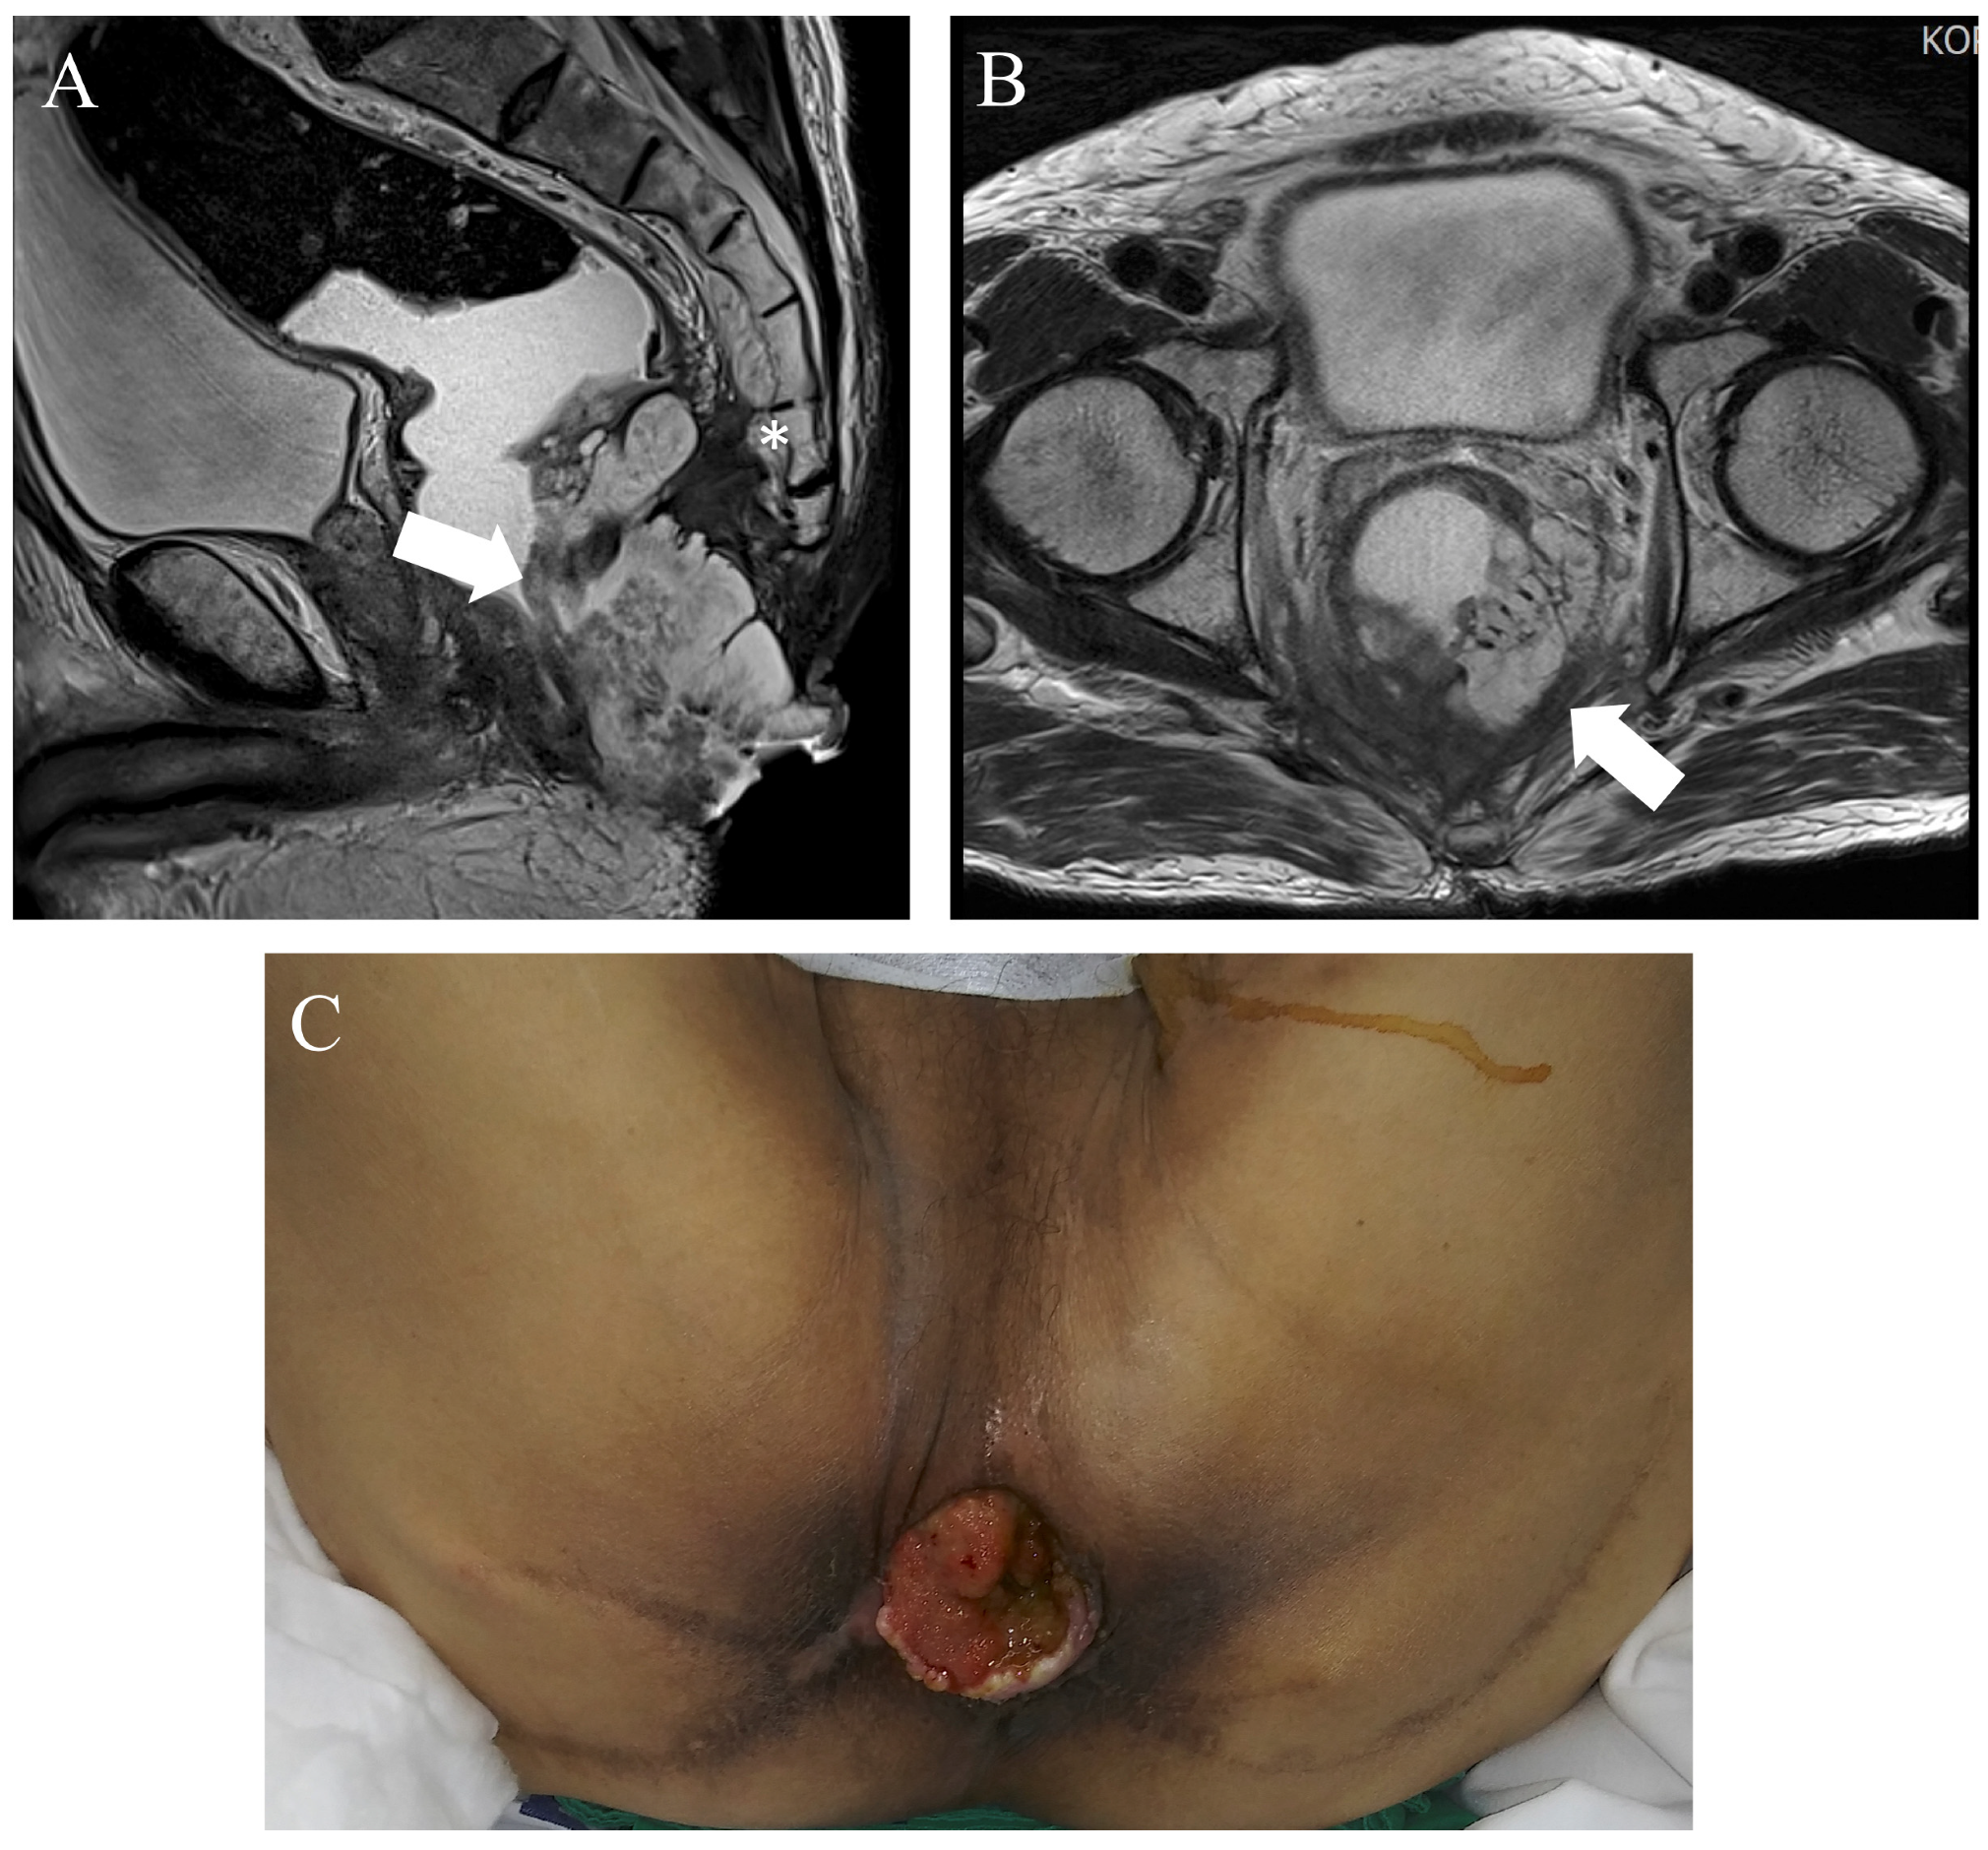

3.3. Case 3: Advanced Anal Cancer